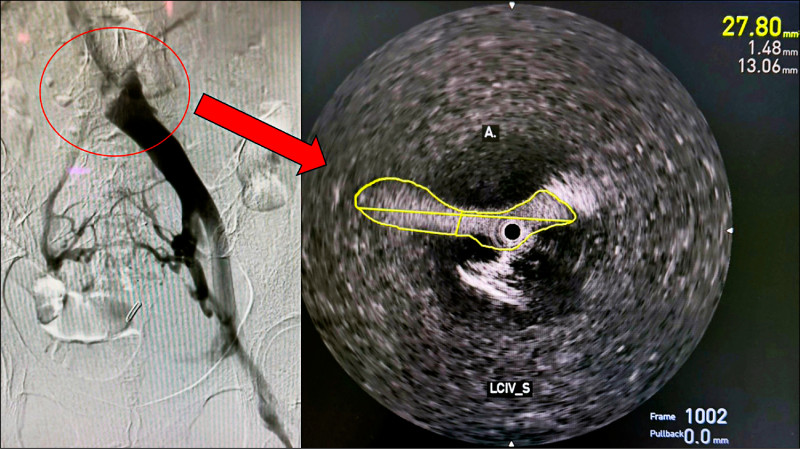

經就醫後,她才發現真正的問題是潛藏性的「深層靜脈狹窄」與「靜脈壓力異常」。長期的靜脈回流障礙導致皮膚循環不良,進而誘發類似血管炎的皮膚反應。

類固醇無效 改微創靜脈支架治療

經評估後,她接受了微創靜脈支架手術。術後短短3個月內,左腿紅疹與腫脹改善9成以上,類固醇與藥膏逐步停用,甚至能重拾慢跑習慣。更讓她驚喜的是,長年困擾的肩頸僵硬、頭痛與夜間平躺背痛,也一併緩解。